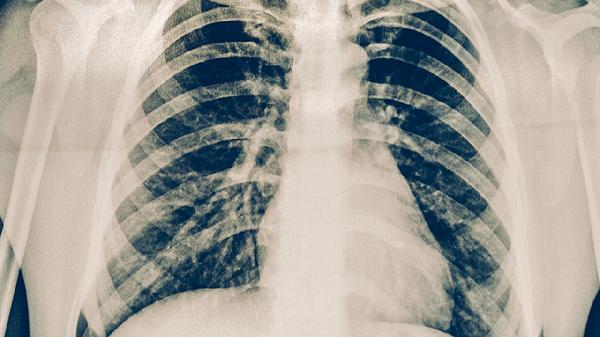

就医后,医生通常会建议进行一系列检查以明确诊断。胸部CT检查能清晰显示肺部结核病灶的变化、有无胸膜受累或气胸。心电图和心肌酶谱检查有助于排除心脏原因引起的胸痛。肝功能检查至关重要,因为多种抗结核药物可能引起肝损伤,导致右上腹或胸部不适。根据胸痛特点和检查结果,医生才能准确判断胸痛根源。